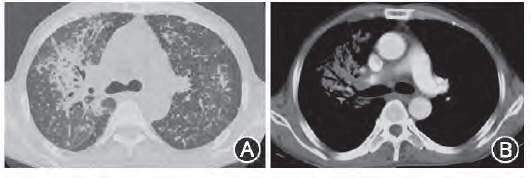

病例1:青少年男性,15岁,以“咳嗽、发热1个月”起病,伴胸闷气短、乏力。既往有1型糖尿病史13年,给予胰岛素控制血糖,入院查血红蛋白">糖化血红蛋白12.7%,痰菌阳性,血抗结核抗体阳性,TB—SPOT(SFCs/106 PBMC):A 616;B 96均为阳性,胸部CT示病变较广泛,上中下叶均受累,双肺多叶多段病变,多种病变形态共存,有空洞及干酪实变(图1)。

图1 胸部CT示病变较广泛,上中下叶均受累,双肺多叶多段病变,多种病变形态共存,有空洞及干酪实变